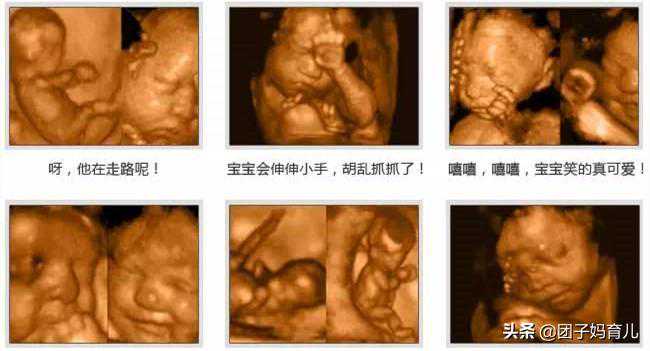

你知道吗?宝宝在肚子里的时候,就已经会笑了怀孕时准妈妈只能感受到胎动,如果想看到宝宝表情只能通过B超或者四维检查时的图像。

孕期的这4种情况,会让胎儿“笑出来”肚子里的小宝宝并不是什么都不懂,他们会有很多的表情和动作,如果产检时幸运的话,还会拍到宝宝可爱的表情。

胎儿在肚子里时还有哪些“技能”?胎宝宝其实还会很多“技能”,并不只是笑笑这样简单哦。

他们感觉到困了就睡觉,无聊的时候他会玩脐带、吃手指、“偷听”爸爸妈妈说话,“踢”妈妈的肚子互动。